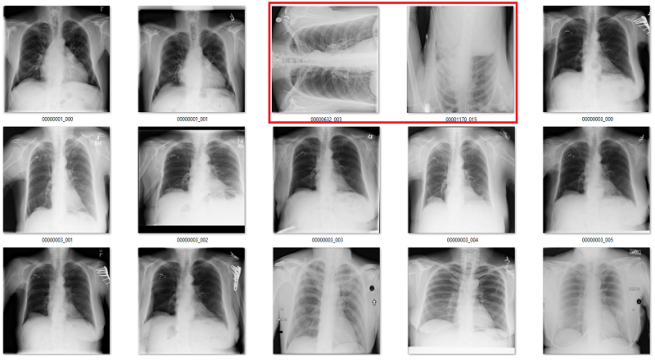

Depending on the manufacturer, you might end up with horizontally or vertically flipped images. They might have inverted pixel values. They might be rotated. The question is, when dealing with a huge dataset (say, 50-100k images), how do you find these aberrations without having a doctor look at all of them?

There are black borders at the sides of many chest x-rays (since most chests are taller than they are wide), so if there are more than 50 black pixel rows along the bottom, it is probably rotated 90 degrees

But as always, we run into failure modes.

Only the middle image here has the classic “black borders at the sides” appearance.

These brittle rules cannot solve these problems for us.

But in medical data, many problems are really easy. There is very little variation. The anatomy, angles, lighting, distance, and background are all pretty stable. To show this, let’s look at a simple example from CXR14. Among the normal chest x-rays in the dataset, there are some that are rotated (and this is not identified in the labels, so we don’t know which ones). They can be rotated 90 degrees left or right, or 180 degrees (upside down).

The difference between rotated and upright chest x-rays is really, embarrassingly simple.

The answer is yes. Visually, the abnormal studies are totally different from the normal studies. You could use a simple visual rule like “the shoulders should be above the heart” and you will get every example right. Given that anatomy is very stable, and all people have shoulders and hearts, this should be a learnable rule for a convolutional net.

Examples of rotated chest films.